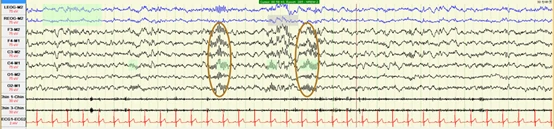

睡眠纺锤波(Sleep Spindle)

频率为12-14Hz,持续时间至少为0.5s,呈现为成串出现的正弦波,常出现于中央区。

慢波(Slow waves)

通常是0.5-2Hz,且振幅大于75μv,呈现为尖或者圆滑的正弦波。常出现于中央区。